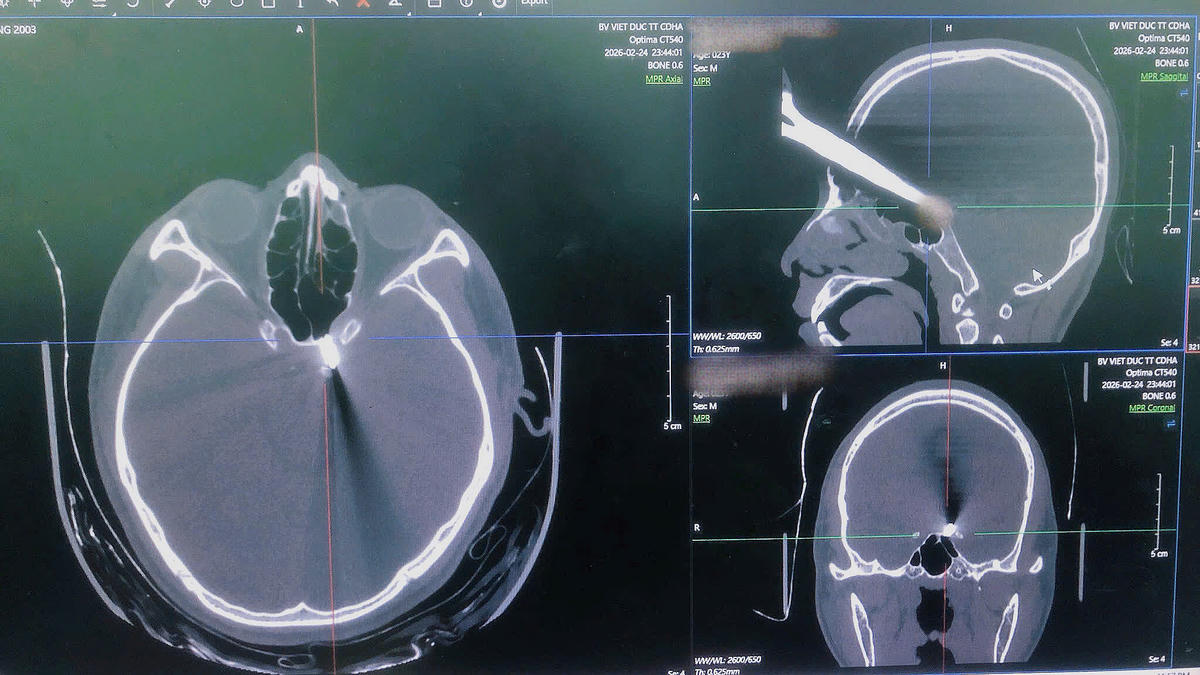

Người bệnh được đưa vào viện trong tình trạng cấp cứu khẩn cấp, với một chiếc kéo rất dài cắm sâu vào não vùng trán, nguy cơ tổn thương nghiêm trọng đến não bộ và để lại những di chứng nặng nề cho người bệnh.

Trực tiếp tham gia cấp cứu và phẫu thuật là BSCKII Đoàn Quang Dũng, Phó Trưởng khoa Phẫu thuật Thần kinh II, cùng ê-kíp trực cấp cứu. Người bệnh được đánh giá nhanh tình trạng tổn thương, thực hiện các cận lâm sàng cần thiết. Kết quả chụp cắt lớp vi tính đa dãy cho thấy đầu nhọn của dị vật (kéo) nằm sát động mạch cảnh trong bên trái, chưa loại trừ tổn thương mạch. Đây là tình huống cực kỳ nguy hiểm, đòi hỏi xử trí nhanh chóng nhưng cũng phải cực kỳ chính xác vì trong quá trình rút dị vật có thể làm động mạch tổn thương thêm và đe doạ ngay lập tức tính mạng bệnh nhân. Ngay lập tức, bệnh nhân được chuyển lên phòng mổ chuyên khoa với những trang thiết bị tiên tiến nhất.